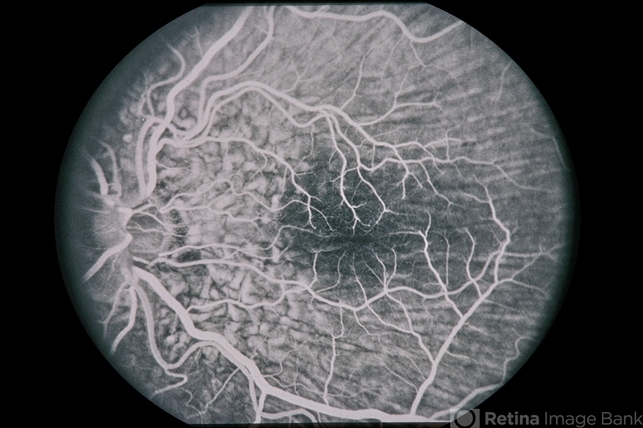

45-year-old Hispanic male with hypotony from over-filtration.